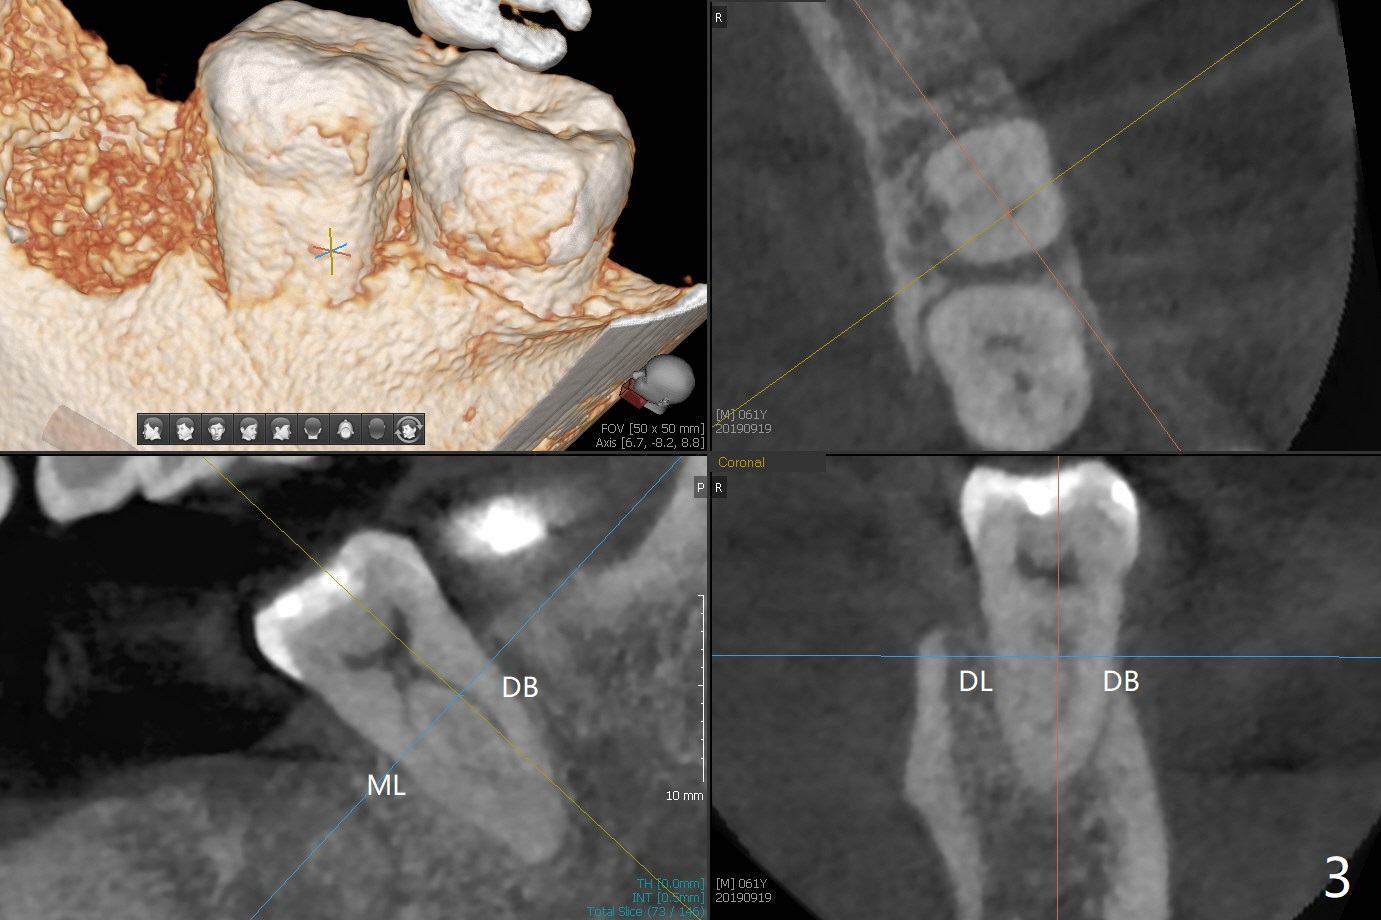

A 61-year-old man may have referral pain between #17 and 18. The canals at #18 are narrower than those at #17 (Fig.1-3). If #18 needs RCT, blocks should be removed (Fig.4-6 vs. 4'-6').